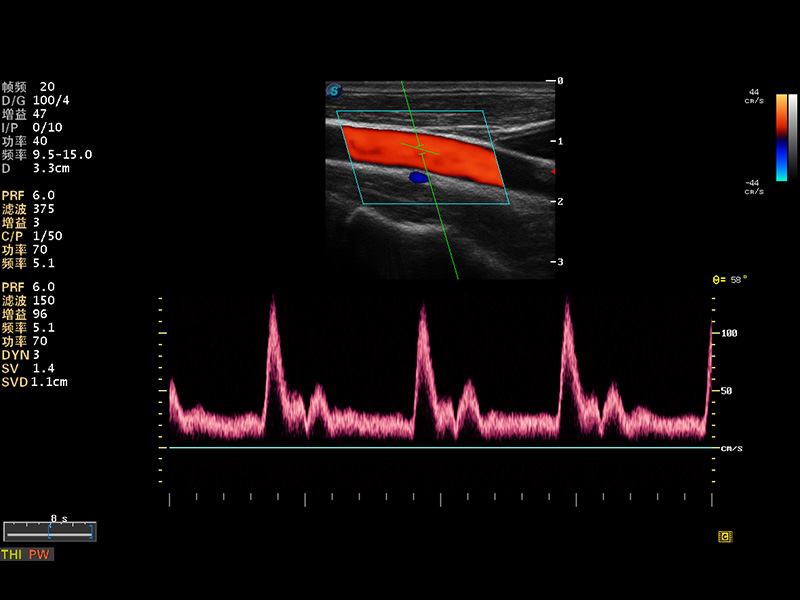

S8 EXP便携式彩色多普勒超声诊断仪是狗万官方网站研发的高端全身应用型便携彩超。高通道的VIS平台融合可视化(Visual)、智能化(Intelligent)和人性化(Smart)的特点,配以狗万官方网站自主研发生产的探头大家族,使您能够快速、准确的获得病人信息,提高工作效率的同时减轻疲劳。

成像技术

多波束形成器

μ-Scan微米成像

谐波成像

实时宽景成像

空间复合成像

3D/4D成像